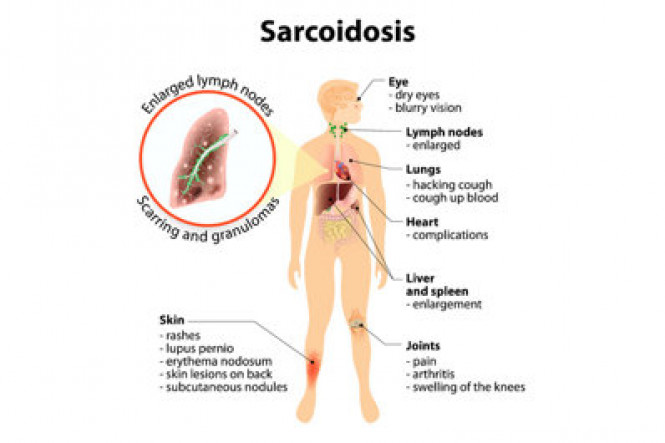

Respiratory diseases

Respiratory diseases are conditions that affect any of the processes involved with breathing. If you or someone you know are one of the 1 in 6 New Zealanders that lives with a respiratory condition, here you can find some useful information on how to manage the condition well.